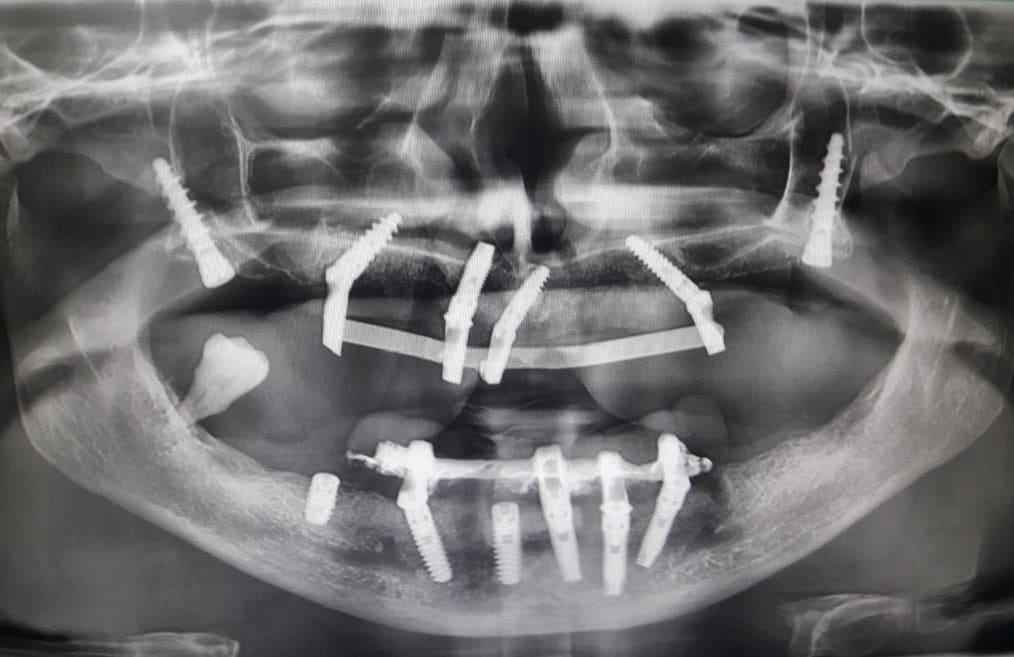

Il nostro team valuta attentamente le condizioni del paziente, registrando le zone con riassorbimenti anomali, atrofie e quelle dell’osso non longilineo. In un’interfaccia diretta tra implantologo e protesista, affrontiamo ogni aspetto negativo, creando un piano personalizzato per il ripristino della masticazione.

Collaborazione Implantologo-Protesista:

La stretta collaborazione tra implantologo e protesista è essenziale per garantire un risultato estetico garantito. Ogni passo del processo è sincronizzato per creare un sorriso che rispecchi le aspettative estetiche e funzionali del paziente.

Ulteriore caso clinico